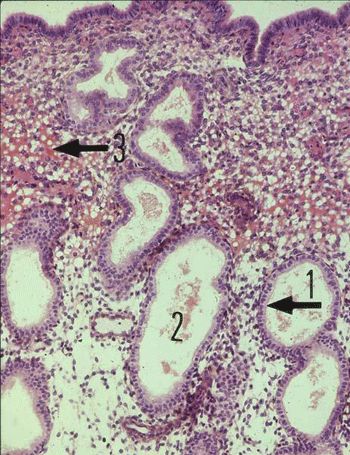

Phase sécrétoire utérine

(Photo : webapps.fundp.ac.be)

Le corps jaune sécrète de la progestérone, ce qui pour effet de développer davantage la muqueuse utérine.

La morphologie de l'endomètre le fait comparer à de la dentelle, d'où le nom de dentelle utérine (ou endométriale) à ce stade. Il est oedématié par l'accumulation de fluide interstitiel (3).